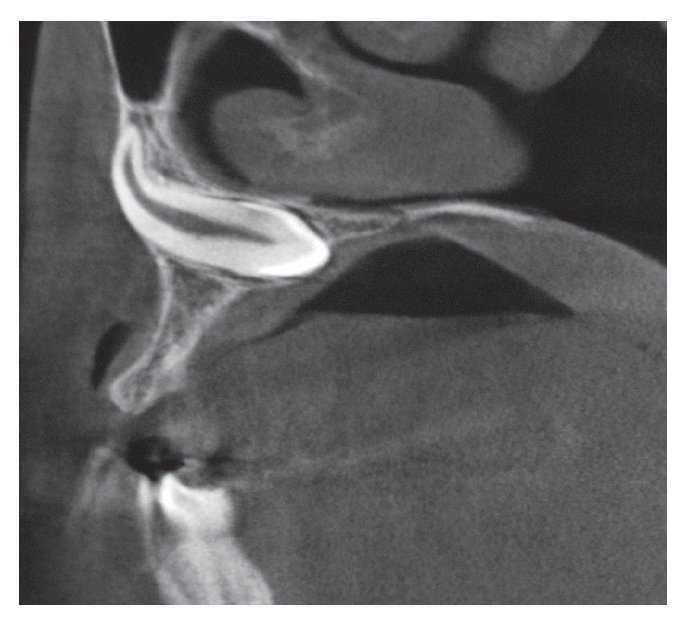

Se obtuvo una tomografía volumétrica digital dental para evaluar una posible movilización del diente 13. En la reconstrucción panorámica (fig. 1) se visualiza el diente 13 muy desplazado en sentido craneal, situándose inmediatamente debajo y cerca de la línea media del seno maxilar derecho. En el plano axial (fig. 2) se observa que la parte coronal del diente ha sufrido una malrotación hacia distal. La reconstrucción sagital (fig. 3) muestra un fragmento apical de la raíz del diente 13 muy curvado hacia craneal.

Figura 3. Tomografía volumétrica digital dental: plano sagital.